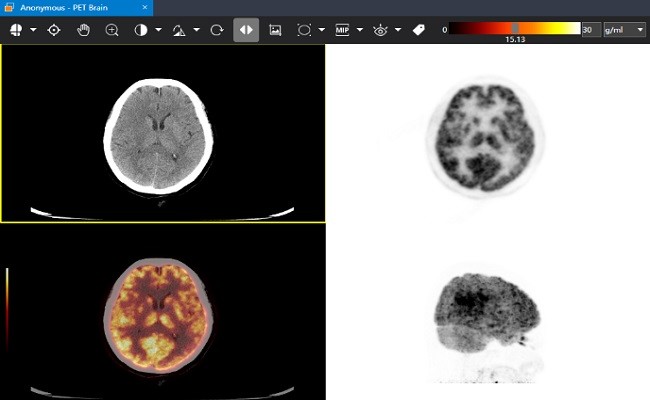

医学影像,用小赛看看。小赛看看DICOM Viewer是一款免费的医学影像DICOM浏览器。支持PET-CT图像融合,MPR浏览,SUV测量,DICOM文件匿名化,DICOM Tag查看等功能。

专业的核医学图像融合功能,支持SPECT/CT、PET/CT、PET/MR融合

支持PET-CT影像的融合显示

支持测量SUV值,CT值